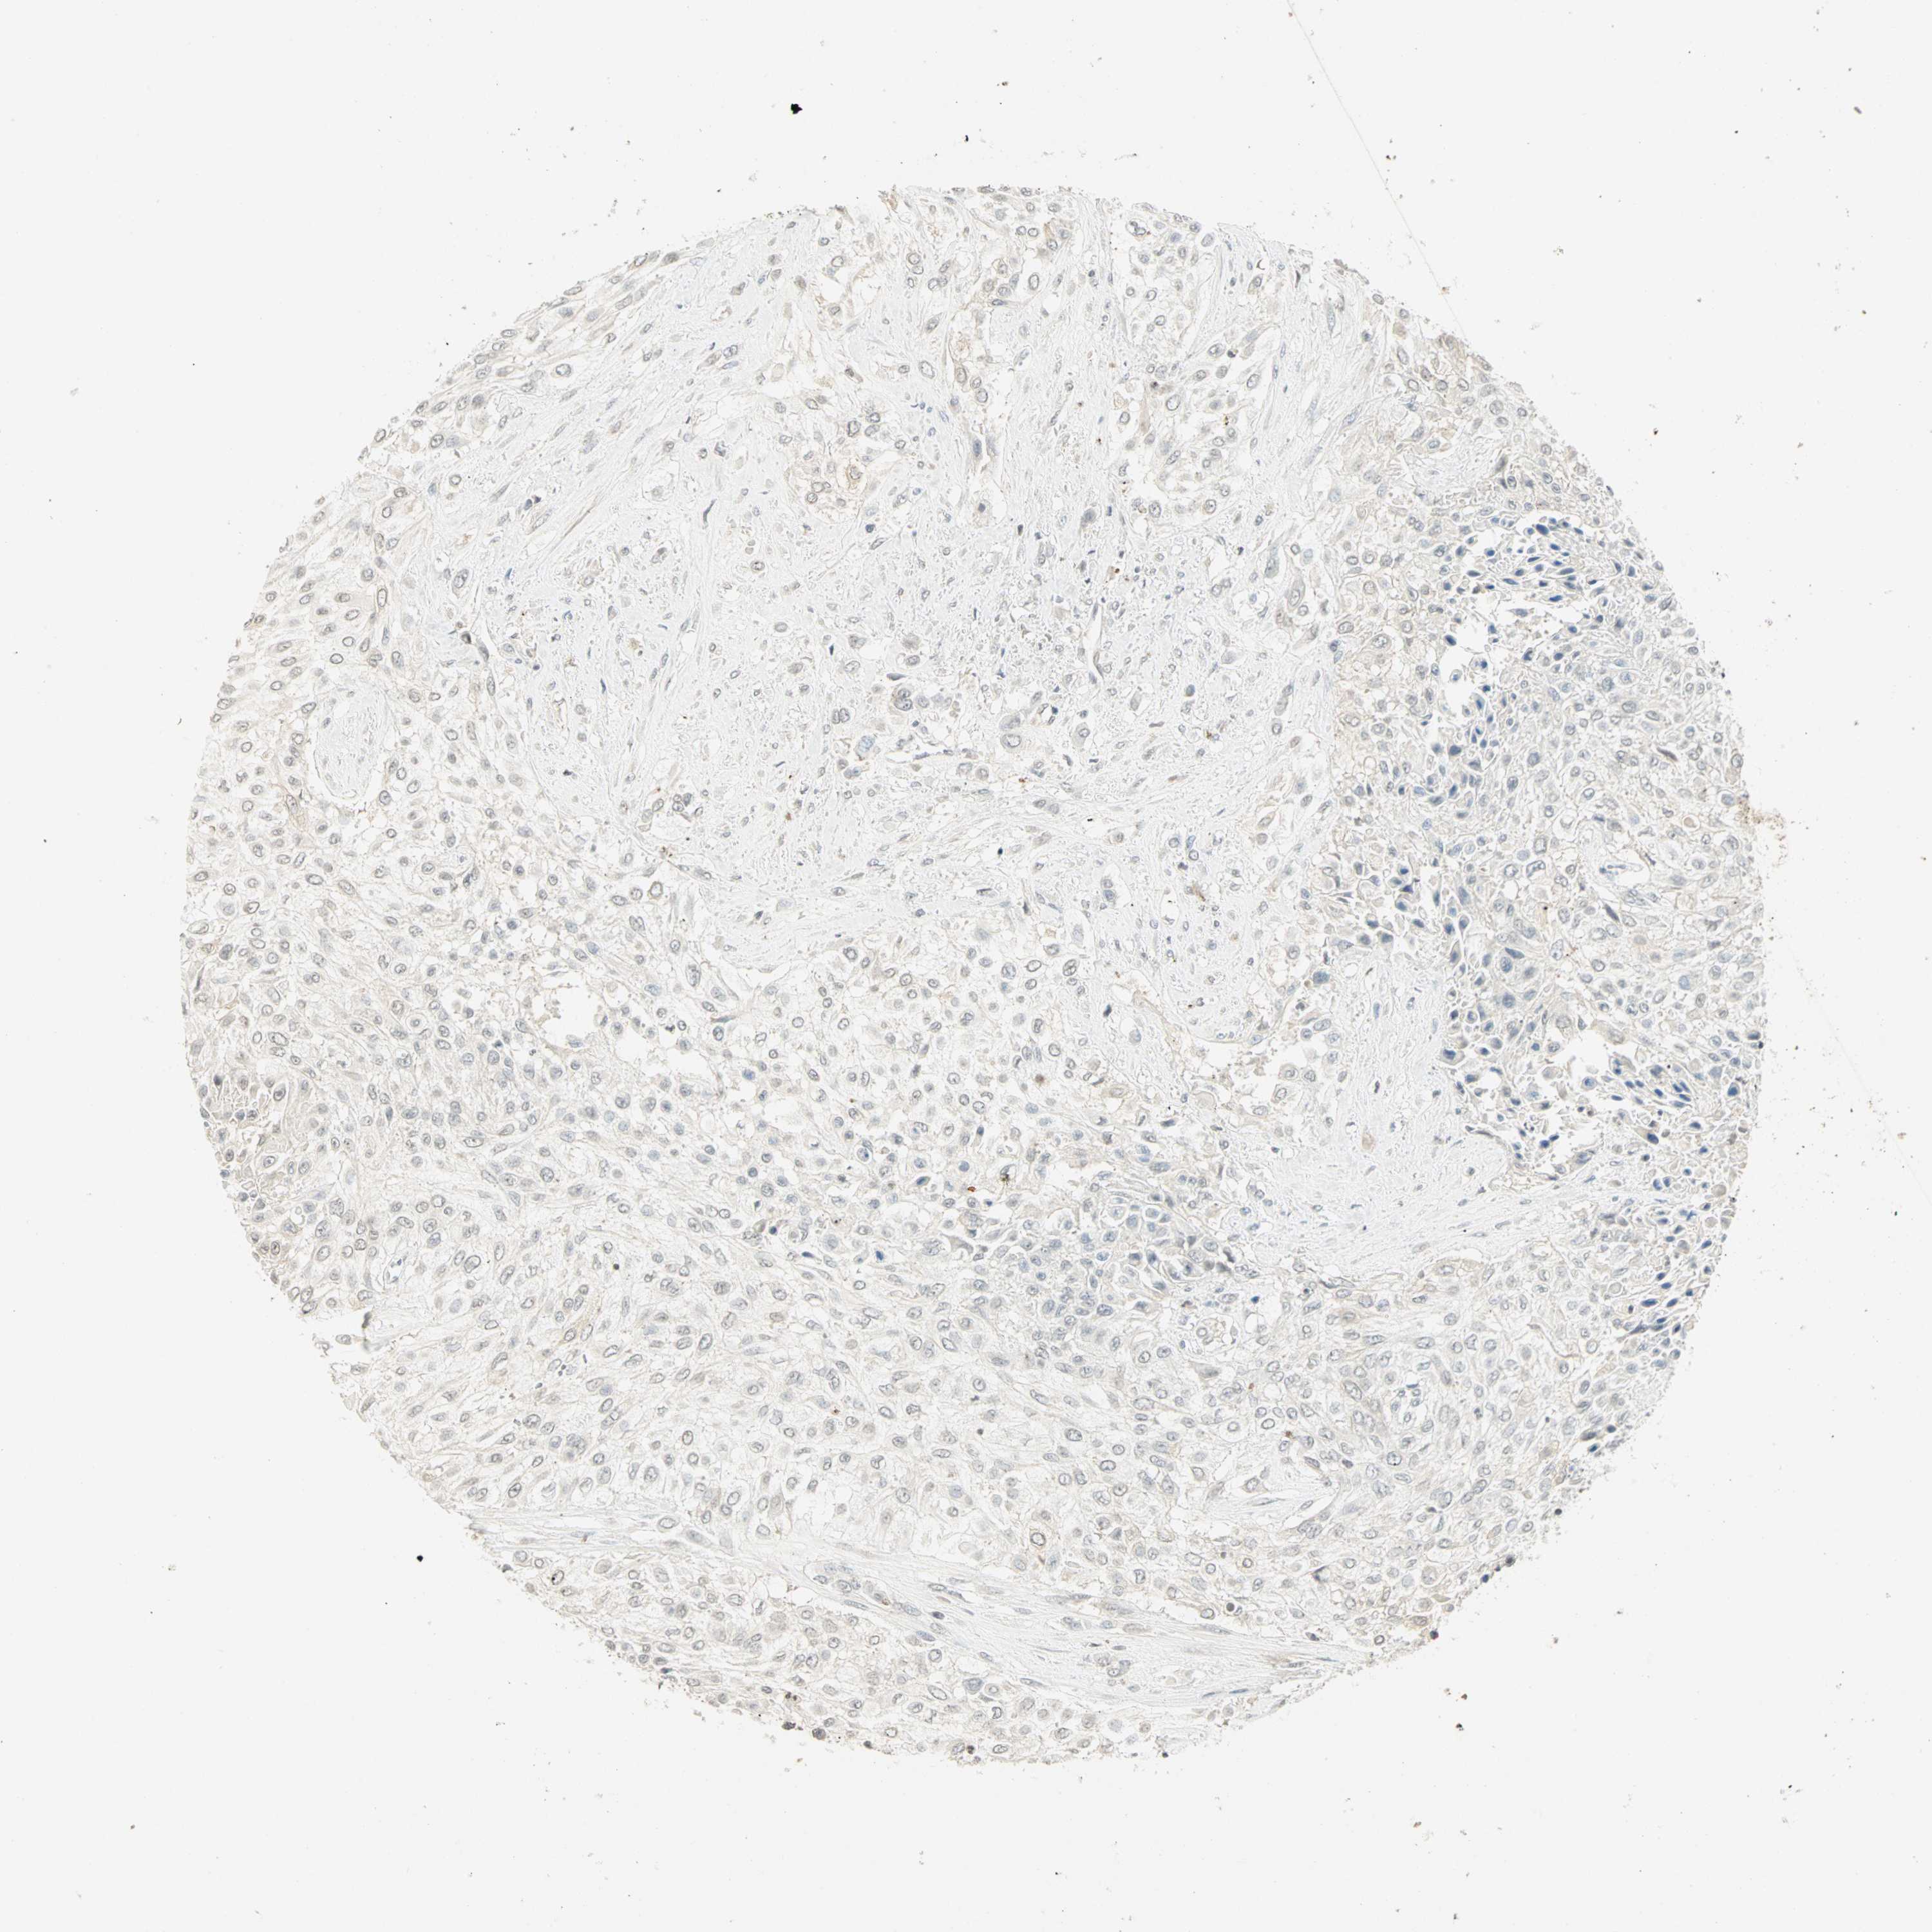

UROTHELIAL CANCER - Protein expressioni

A mouse-over function shows sample information and annotation data. Click on an image to view it in a full screen mode. Samples can be filtered based on level of antibody staining by selecting one or several of the following categories: high, medium, low and not detected. The assay and annotation is described here.

Note that samples used for immunohistochemistry by the Human Protein Atlas do not correspond to samples in the TCGA dataset.

Antibody stainingi

Antibody staining in the annotated cell types in the current human tissue is reported as not detected, low, medium, or high, based on conventional immunohistochemistry profiling in selected tissues. This score is based on the combination of the staining intensity and fraction of stained cells.

Each image is clickable and will lead to virtual microscopy that enables deeper exploration of all samples and also displays staining intensity scores, fraction scores and subcellular localization as well as patient and tissue information for each sample.

Antibody HPA067203

Antibody CAB008094

Antibody CAB069409

Staining

High

Medium

Low

Not detected

Intensity

Strong

Moderate

Weak

Negative

Quantity

>75%

75%-25%

<25%

None

Location

Nuclear

Cytoplasmic/membranous

Cytoplasmic/membranous,nuclear

Urothelial carcinoma, High grade

Urothelial carcinoma, NOS

Urothelial carcinoma, Low grade